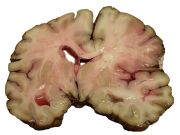

A slice of brain from the autopsy of a person who suffered an acute middle cerebral artery (MCA) stroke